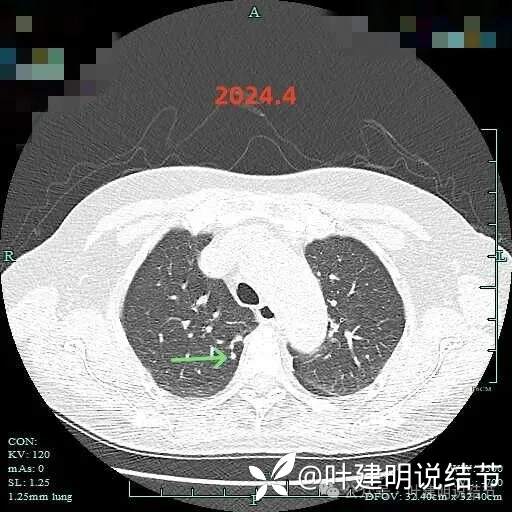

2024年4月右下病灶血管进入明显,整体密度显高,表面稍不平,欠光滑。

右上实性结节密度高,无显著进展,表面相对较光滑。